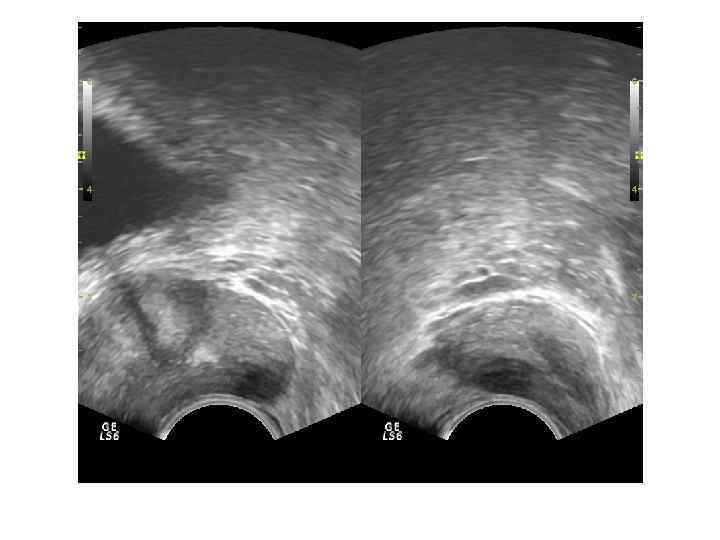

Хронический простатит характеризуется полиморфизмом картины. Различают 4 формы: -отёчная – диффузное увеличение размеров и чередование зон повышенной и пониженной эхогенности с преобладанием гипоэхогенности. -конгестивная (застойная) - диффузная неоднородность структуры - чередование зон повышенной и пониженной эхогенности, отмечается более выраженная дифферецировка анатомо-функциональных зон. Размер железы может быть незначительно увеличен. -калькулёзная - присутствие гиперэхогенных включений чаще без акустической тени. -склеротическая - при которой преобладает диффузное повышение эхогенности и уменьшение размеров.